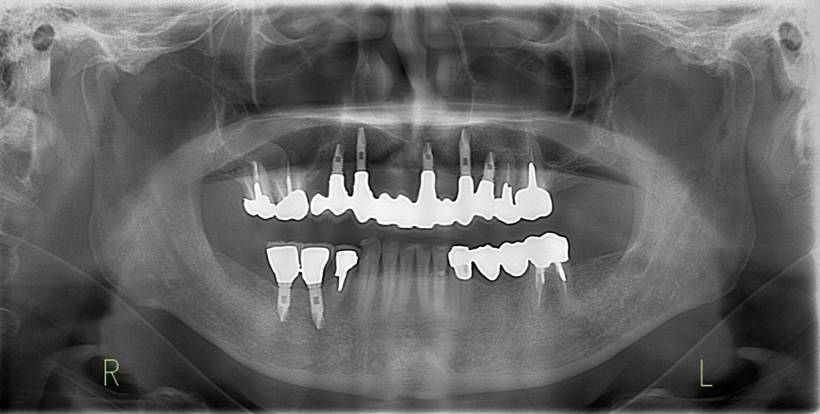

治療後。歯周病で失われた骨が回復しています。使用インプラントはスプラインツイストです。

上部構造装着後6年。ハイブリッドレジンを使用したため、少し艶がなくなってきました。上部構造の材料には金属、ハイブリッドレジン、セラミックなどがあります。セラミックはきれいですが欠けやすいため、最近はフルジルコニアを使っています。

インプラント装着後6年。順調に経過しています。12か月毎のメインテナンスをしています。